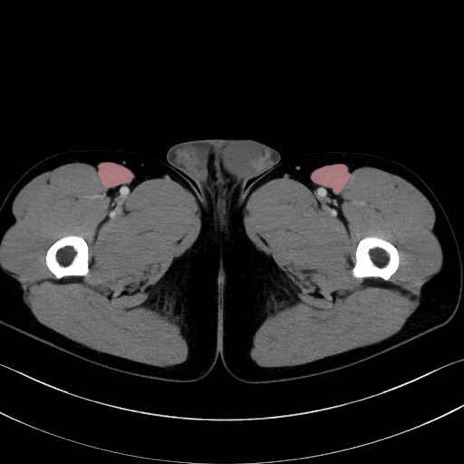

縫工筋 (Sartorius)

大腿直筋 (Rectus femoris)

外側広筋 (Vastus lateralis)

中間広筋 (Vastus intermedius)